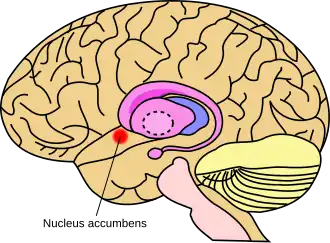

Approximate location of the nucleus accumbens in the brain | |

The nucleus accumbens (NAc or NAcc; also known as the accumbens nucleus, or formerly as the nucleus accumbens septi, Latin for 'nucleus adjacent to the septum') is a region in the basal forebrain rostral to the preoptic area of the hypothalamus.[1] The nucleus accumbens and the olfactory tubercle collectively form the ventral striatum. The ventral striatum and dorsal striatum collectively form the striatum, which is the main component of the basal ganglia.[2] The dopaminergic neurons of the mesolimbic pathway project onto the GABAergic medium spiny neurons of the nucleus accumbens and olfactory tubercle.[3][4] Each cerebral hemisphere has its own nucleus accumbens, which can be divided into two structures: the nucleus accumbens core and the nucleus accumbens shell. These substructures have different morphology and functions.

The nucleus accumbens is an aggregate of neurons which is described as having an outer shell and an inner core.[4]